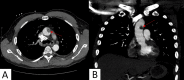

Figure 1. Axial (A) and coronal (B) section of CT pulmonary angiogram. Prominent irregular mural thrombus measuring 2.5 x 1.2 cm in the ascending aortic arch (red arrow).